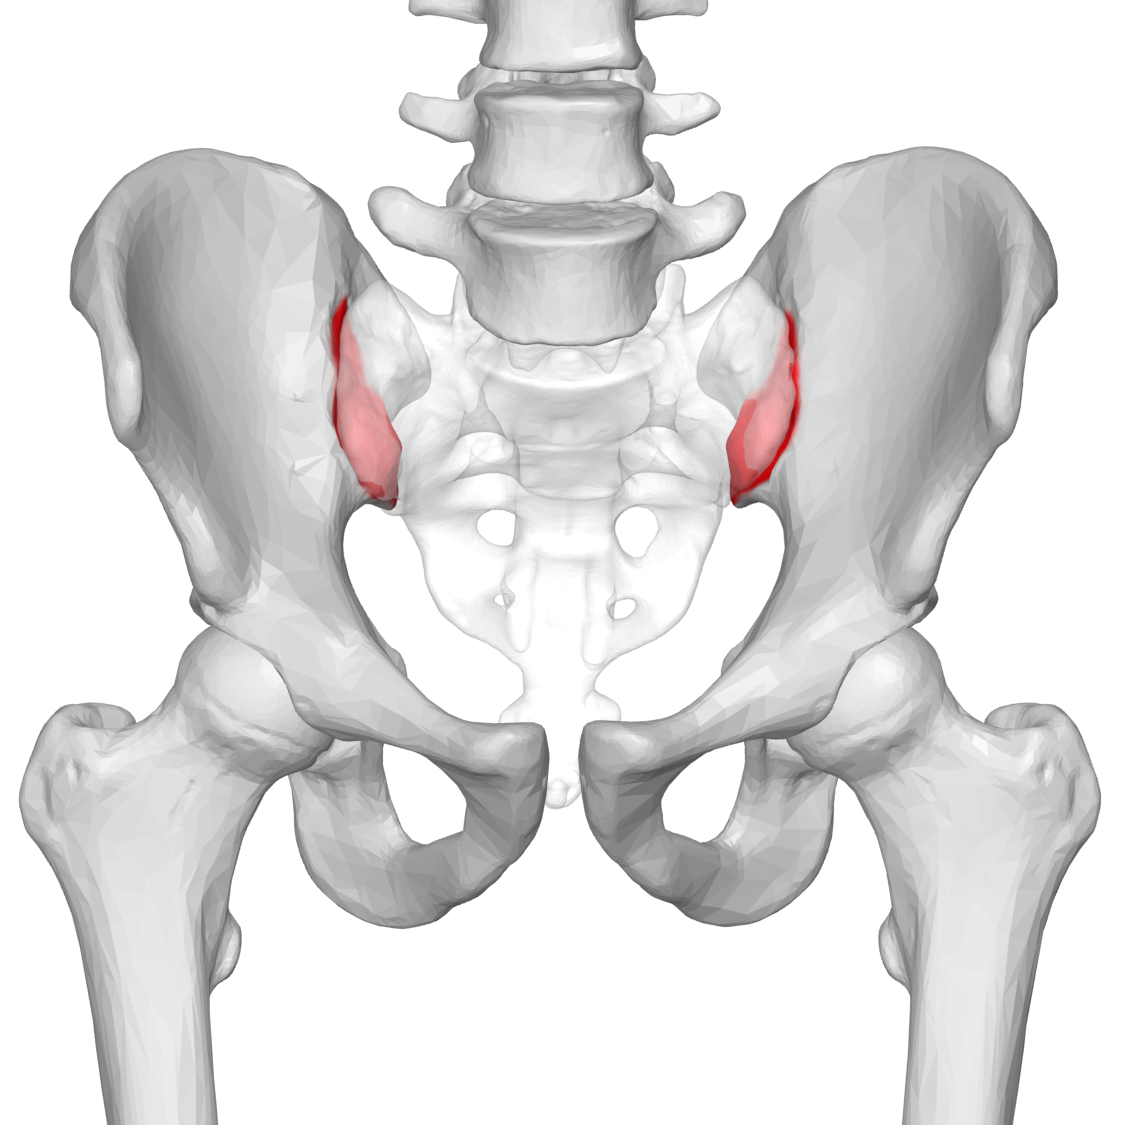

엉치 엉덩관절은 위 그림에서 빨간색으로 표시된 부분입니다.